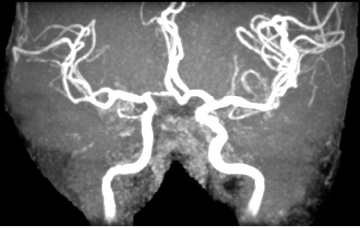

依據衛生署國民健康局於2007年委託進行之「台灣地區高血壓、高血糖、高血脂之追蹤調查研究」結果,50歲之前女性的高血壓、高血糖及高血脂發生率普遍低於同年齡層的男性,但值得注意的是女性在更年期後,三高發生的比率大於男性,顯示女性更年期後,三高是一個不能輕忽之健康議題。(圖:2002至2007年國內民眾不同性別及年齡層之高血壓發生率)